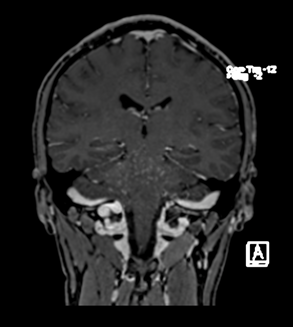

extremidades, marcha atáxica. La RNM de cerebro simple y contrastada evidencia múltiples

lesiones hipointensas en T1, hiperintensas en T2 y FLAIR con realce heterogéneo (patrón

en sal y pimienta) localizadas en puente y hemisferios cerebelosos. LCR documenta

Figura 2

El gold standard es la resonancia magnética de cerebro que puede evidenciar en puente

muestran imágenes puntiformes con aspectos de "sal y pimienta" o curvas con absorción de contraste. (6) Este tipo de lesiones son de mayor predominio puente, pero se pueden

evidenciar en otras regiones SNC, como cerebelo. (5). Este tipo de lesiones no suelen ser

mayor a 3 mm de diámetro, con un patron de distribución el cual disminuye en número al

alejarse de la protuberancia, pero pueden extenderse al cerebro y médula espinal.(3)

Los criterios de imagen incluyen los siguientes:

1.Nódulos homogéneos que mejoran el gadolinio sin realce del anillo ni efecto de

masa que predominan en el puente y el cerebelo, que miden <3 mm de diámetro